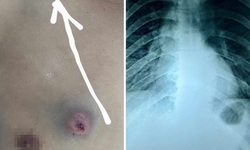

Y tế - 29/07/2025 19:24SKĐS - Đang làm vườn tại nhà, người phụ nữ 40 tuổi ở Cần Thơ bất ngờ bị vật thể lạ bay trúng đầu, gây chảy máu. Tại bệnh viện, bác sĩ phát hiện dị vật là một đầu đạn kim loại còn nằm dưới da vùng chẩm.